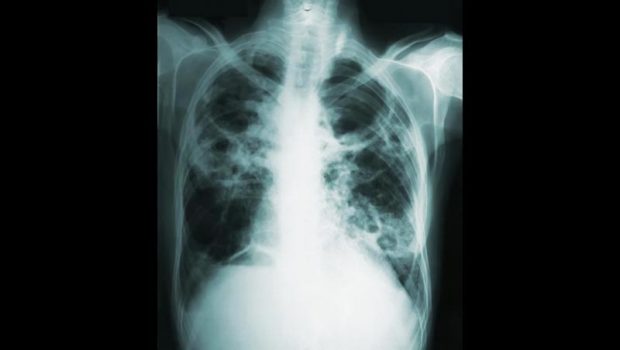

DSÖ: 2023’te 8,2 milyon kişiye tüberküloz teşhisi konuldu

Dünya Sağlık Örgütü (DSÖ) Genel Direktörü Tedros Adhanom Ghebreyesus, 2023’te dünya genelinde 8,2 milyon kişiye tüberküloz teşhisi konulduğunu söyledi.

DSÖ’nün tüberküloz hastalığıyla ilgili yıllık raporunu yayınladığını kaydeden Ghebreyesus, “2023’te 8,2 milyon kişiye tüberküloz teşhisi konuldu.” dedi.

Ghebreyesus, bunun, DSÖ’nün 1995’te, küresel tüberküloz durumunu takip etmeye başlamasından bu yana kaydedilen “en yüksek” sayı olduğunu belirtti.

Kovid-19 salgınının neden olduğu aksaklıkların ardından önleme, teşhis ve tedavi hizmetlerine erişimin iyileşmeye devam ettiğini aktaran Ghebreyesus, tüberküloza bağlı can kaybı sayısında üst üste ikinci yıl düşüş yaşandığını ifade etti.